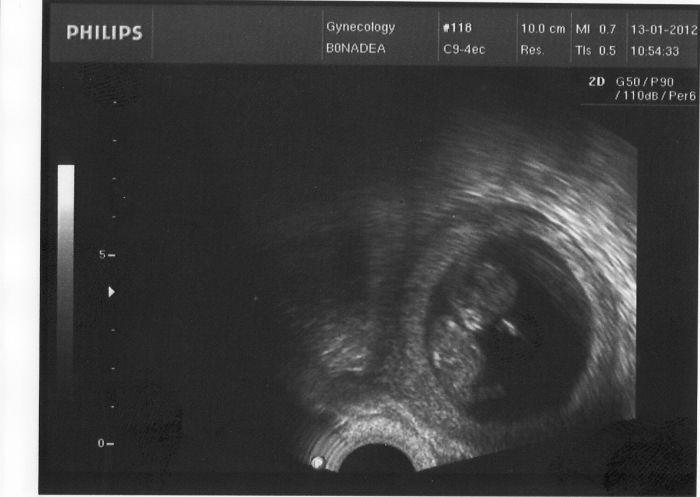

Ahoj holky, tak jsem byla konečně na první návštěvě doktorky, všechno je v pořádku

Srdíčko bouchá jak má, už se začíná dělat placenta, takže doufám, že konečně budu v klidu spát. I já mám fotku, tak se musím pochlubit, je dělaná vnitřkem.

Ahojky Lucce27 moc gratuluju, fotka je nádherná, já už se nemůžu dočkat až budu mít taky takovou budu si muset počkat až do 26.ledna a příjde mi to nekonečný... jen aby bylo vše v pořádku.a v kolikátým si prosím týdnu?